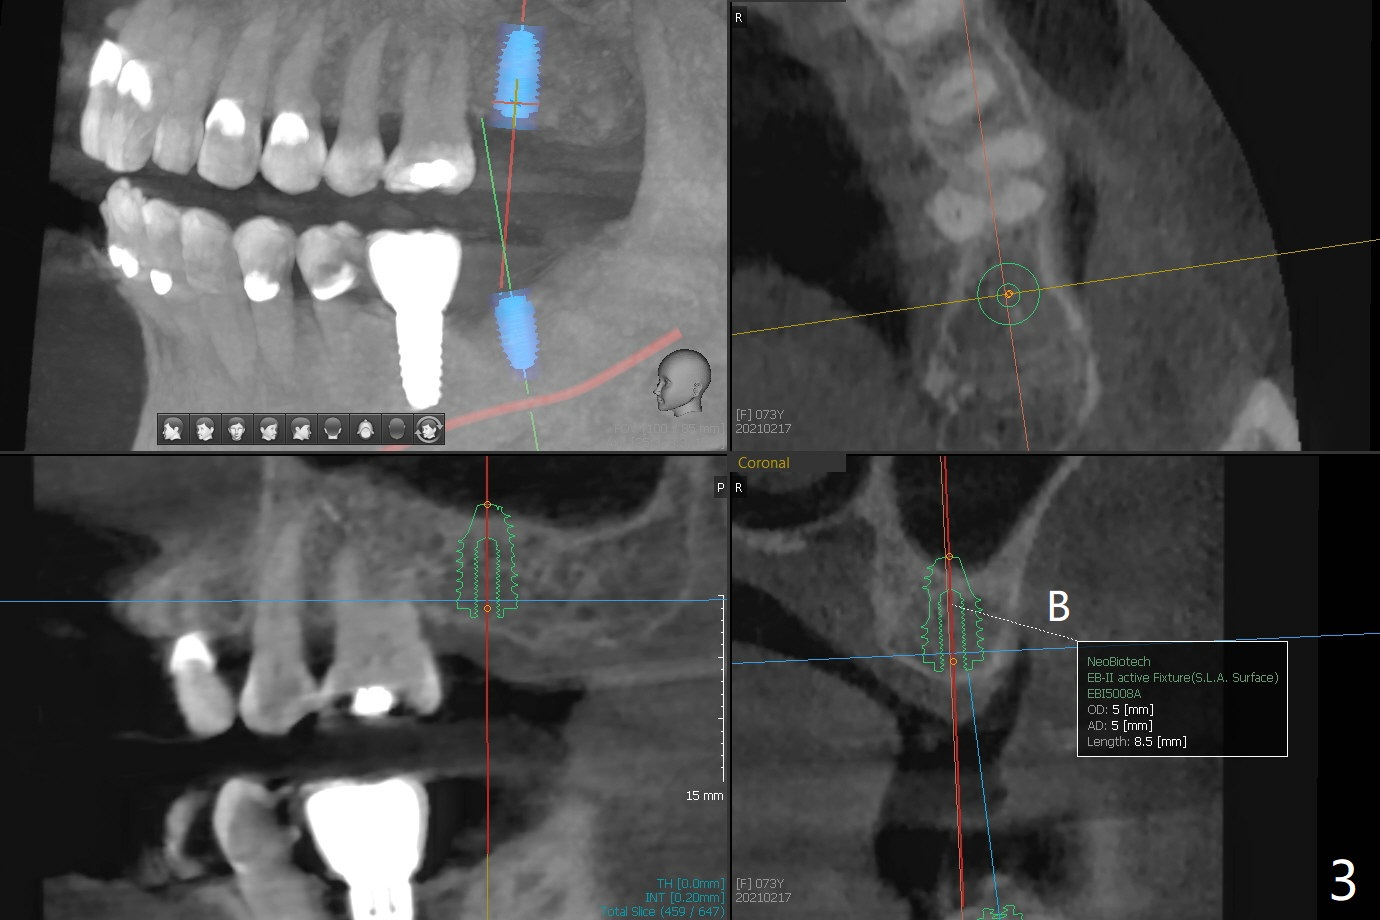

A 73-year-old woman with sign of occlusal wear breaks a lingual cusp of #31. After restoration, she agrees to have implants at #15 and 18 (Fig.1-3).